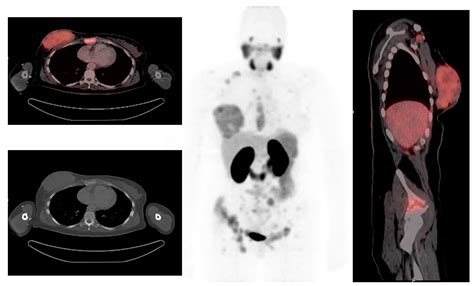

At its core, a Pet Ct scan is designed to provide both functional and structural information. While a traditional CT scan uses X-rays to create detailed pictures of organs and tissues, a PET scan uses a small amount of radioactive tracer to highlight areas of high metabolic activity. This is particularly crucial in oncology, as cancer cells often exhibit higher metabolic rates than healthy cells.

When these two technologies are combined into a single Pet Ct machine, the results are fused together. This allows doctors to pinpoint the exact location of a biological abnormality and observe its physical size and shape simultaneously. The fusion of this data is what makes it a gold standard in modern diagnostics.